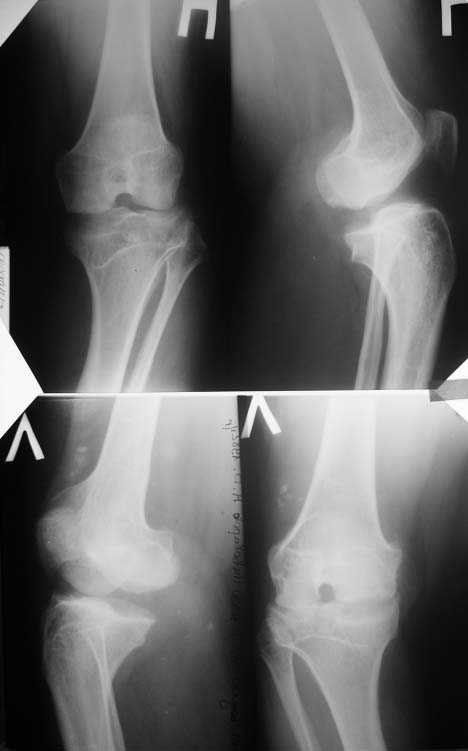

Прямая и боковая обоих коленных суставов

По одной рентгенограмме тазобедренного сустава сложно ответить на вопрос о возможности протезировния (коленных особенно).

Коленный сустав в 2-х проекциях, а в идеальном случае - осевой снимок всей нижней конечности.

Алексей, судя по снимкам, правый тазобедренный сустав нуждается в замене. Думаю, что получится поставить протез без дополнительных конструкций во впадину и особых ножек. Важным является диаметр канала. Надо по шаблонам оценить размер. Самые маленькие из известных мне ножек в России предсталены у De Puy (бесцементная 6), и новинка от BIOMET бесцементная диспластическая ножка.

О коленях надо больше клинической информации, а главное чего хочет сам пациент.